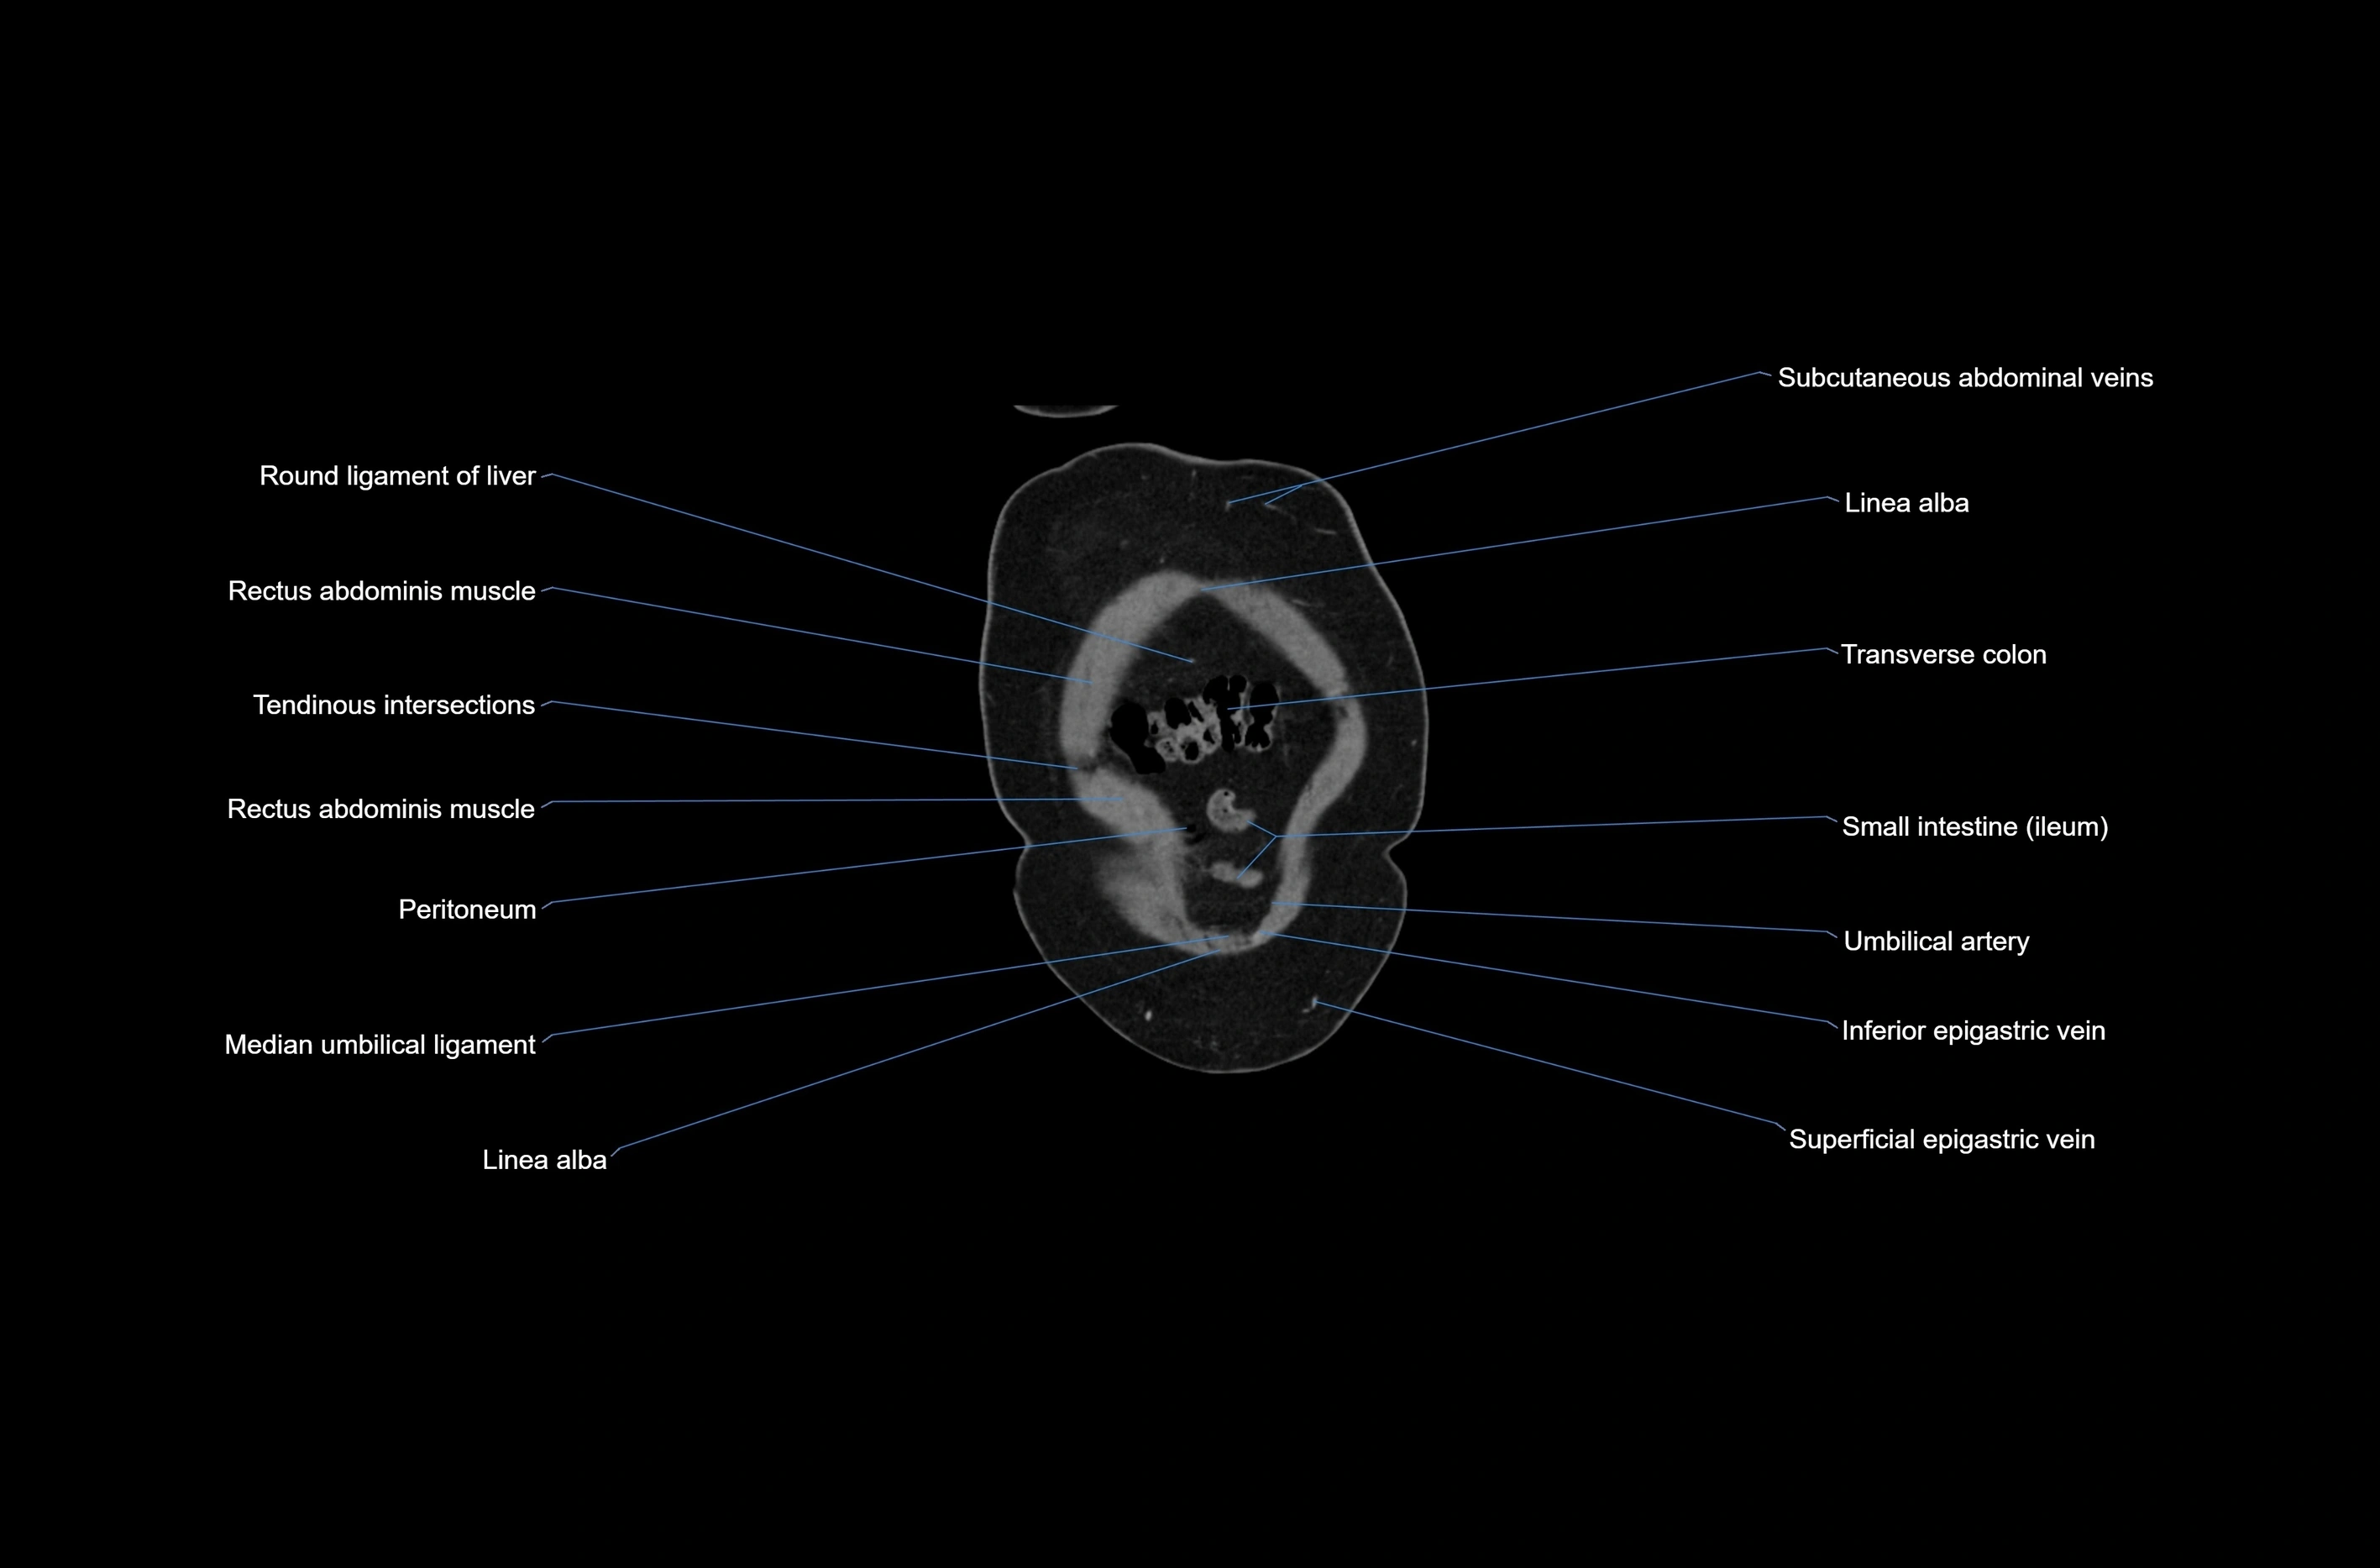

CT images